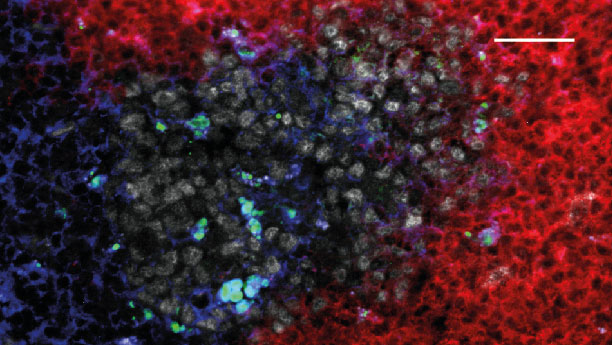

Autoimmunerkrankungen wie die Rheumatoide Arthritis sind durch schwerwiegende entzündliche Prozesse an Gelenken und inneren Organen gekennzeichnet. Die Ursachen für den Ausbruch und den meist schubweisen Verlauf solcher Erkrankungen sind bisher unzureichend verstanden. Ein internationales Forscherteam um Prof. Dr. G. Krönke an der Medizinischen Klinik 3 hat einen neuen Mechanismus identifiziert, der unmittelbar für den Ausbruch von Autoimmunerkrankungen verantwortlich ist. Hierbei scheint das Fehlen von bestimmten Zuckermolekülen an den für die Rheumatoide Arthritis verantwortlichen Eiweißstoffen ausschlaggebend zu sein. Ihre Ergebnisse haben die Forscher im renommierten Fachjournal Nature Immunology veröffentlicht.

Die Arbeitsgruppe von Prof. Dr. G. Krönke konnte in Zusammenarbeit mit anderen Wissenschaftlern der FAU und einem internationalen Forscherteam aus den Niederlanden, Schweden und Österreich nun erstmals zeigen, dass eine bestimmte Gruppe von Immunzellen, die TH17-Zellen, direkt auf das immunologische Gedächtnis einwirkt und durch eine scheinbar harmlose Veränderung der molekularen Struktur von Autoantikörpern den Ausbruch einer Autoimmunerkrankung provoziert. Réné Pfeifle, Doktorand an der Medizinischen Klinik 3 und Erstautor der Studie, berichtet:

Tatsächlich ist für den Ausbruch von Autoimmunerkrankungen wie der Rheumatoiden Arthritis in diesem Fall nur das Fehlen eines einzigen Zuckermoleküls an den jeweiligen Autoantikörpern verantwortlich.

Während bisherige Therapien der Rheumatoiden Arthritis auf die Hemmung der Entzündungsreaktion abzielen, können diese neuen Erkenntnisse in Zukunft dazu dienen, völlig neue Therapieansätze zur Verhinderung des Ausbruchs von Autoimmunerkrankungen zu entwickeln. Hierbei soll das Immunsystem jedoch nicht gehemmt, sondern durch gezielte Modulation von TH17-Zellen einer Art Reprogrammierung unterzogen werden. Mit Hilfe einer solchen Strategie wiederum könnten die krankheitsauslösenden Veränderungen der Zuckerstruktur von Autoantikörpern rückgängig gemacht werden und somit Immuntoleranz und eine langfristige Heilung von Autoimmunerkrankungen ermöglicht werden.